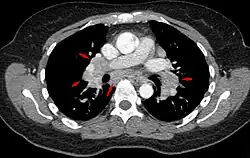

CT scan of the chest showing lymphadenopathy (arrows) in the mediastinum due to sarcoidosis

Diagnosis of sarcoidosis is a matter of exclusion, as there is no specific test for the condition other than the Kveim-Siltzbach test. To exclude sarcoidosis in a case presenting with pulmonary symptoms might involve a chest radiograph, CT scan of chest, PET scan, CT-guided biopsy, mediastinoscopy, open lung biopsy, bronchoscopy with biopsy, endobronchial ultrasound, and endoscopic ultrasound with fine-needle aspiration of mediastinal lymph nodes (EBUS FNA). Tissue from biopsy of lymph nodes is subjected to both flow cytometry to rule out cancer and special stains (acid fast bacilli stain and Gömöri methenamine silver stain) to rule out microorganisms and fungi.[99][100][12][101]

Chest radiograph changes are divided into four stages:[104]

1. bihilar lymphadenopathy

2. bihilar lymphadenopathy and reticulonodular infiltrates

3. bilateral pulmonary infiltrates

4. fibrocystic sarcoidosis typically with upward hilar retraction, cystic and bullous changes